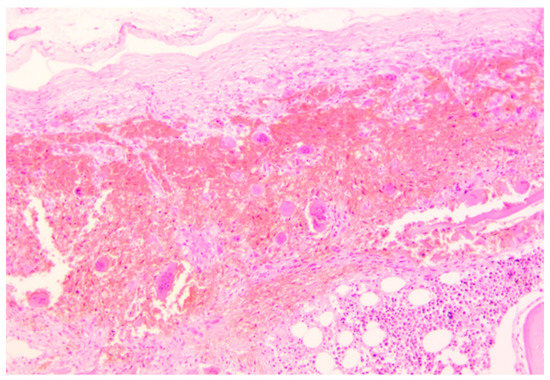

Histopathological analysis was performed on all the specimens collected. Skullcap bone (Figure 3) showed a diffused demineralization with multiple foci of hyperplastic multinucleate osteoclasts and osteofibrosis.

Figure 3.

Skullcap erosion, parietal bone. H&E staining—magnification 40×. Immediately below the external theca of the bone cap is present a large osteolytic hotbed, bone tissue with massive demineralization replaced by granulation tissue, and massive red blood cell infiltration.